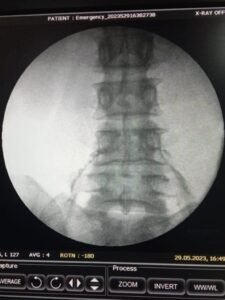

- Epidural Steroid Injections (ESIs): In cases of severe or persistent pain, an ESI may be recommended. This procedure involves injecting a corticosteroid medication directly into the affected area to reduce inflammation and alleviate pain.